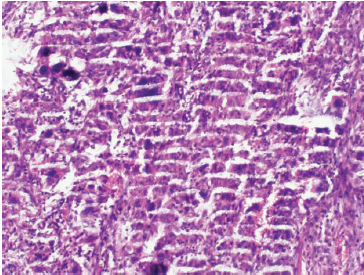

七、切片染色效果不佳

切片染色效果不佳可能是由于染色時(shí)間過(guò)長(zhǎng)或過(guò)短、染色液濃度不合適等原因造成的。